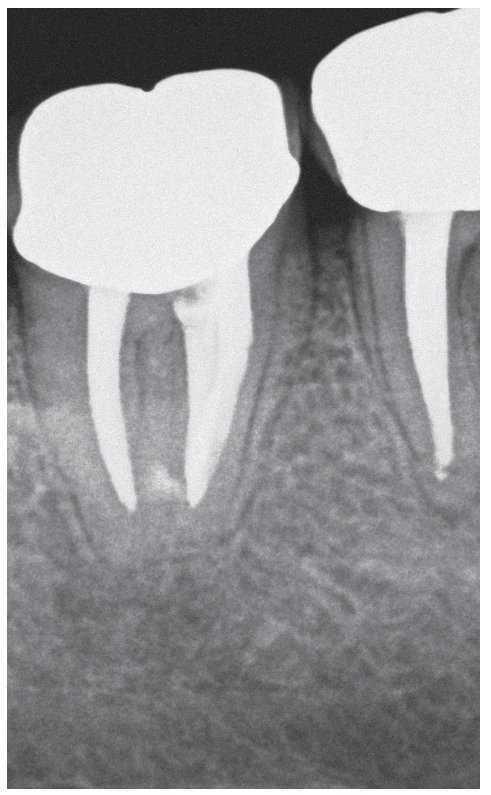

Figura 2a. La radiografía diagnóstica del diente 47 muestra una periodontitis apical postendodóntica.

Figura 2c. Situación después de la apertura cameral: la obturación existente carece de sellado marginal. No se identificó la luz del conducto radicular original. Alrededor del material de obturación se detecta tejido necrótico de aspecto negruzco, sobre todo en la zona distal donde el conducto radicular adopta una forma marcadamente ovalada. Se pasó por alto y no se preparó el istmo frecuentemente existente en los molares inferiores entre el conducto mesiovestibular y el conducto mesiolingual.

Figura 2d. Después de limpiar el suelo de la cámara pulpar salen a la luz las estructuras del sistema de conductos radiculares que se pasaron por alto en el primer tratamiento.

Figura 2e. Situación después del retratamiento de los conductos principales. Se aprecia con claridad el tejido existente en el istmo mesial.

Figura 2f. Situación después de la preparación completa del istmo mesial coronal. Se pudo palpar otro istmo en el tercio medio de la raíz mesial a través del que fluyó líquido de irrigación. Se preparó este istmo mediante instrumentos ultrasónicos.

Figura 2g. Situación después de la obturación termoplástica. Los istmos también muestran un buen sellado marginal.

Figura 2h. Radiografías de control después de la obturación: el tamaño de la luz obturada es considerablemente mayor en comparación con el tratamiento inicial. Se consiguió una obturación homogénea de los dos istmos situados en la parte coronal y apical de la raíz mesial.

Figura 2i. La radiografía de control realizada a los 12 meses mostró una curación ósea completa de la lesión apical.